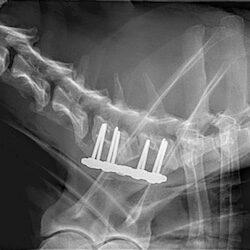

Cutting-edge surgical techniques supported by the latest evidence; TPLO for cruciate ligament tears. Management of patellar luxation, elbow, shoulder, hip & tarsal joint disease, complex fractures & limb deformities.